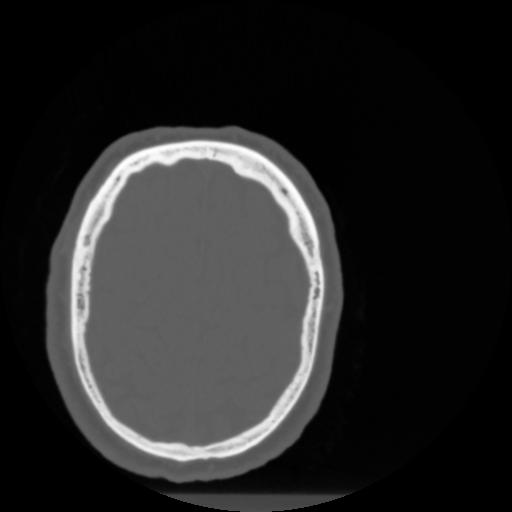

4 CEREBRO,,Vol,0.5,CEREBRO,,